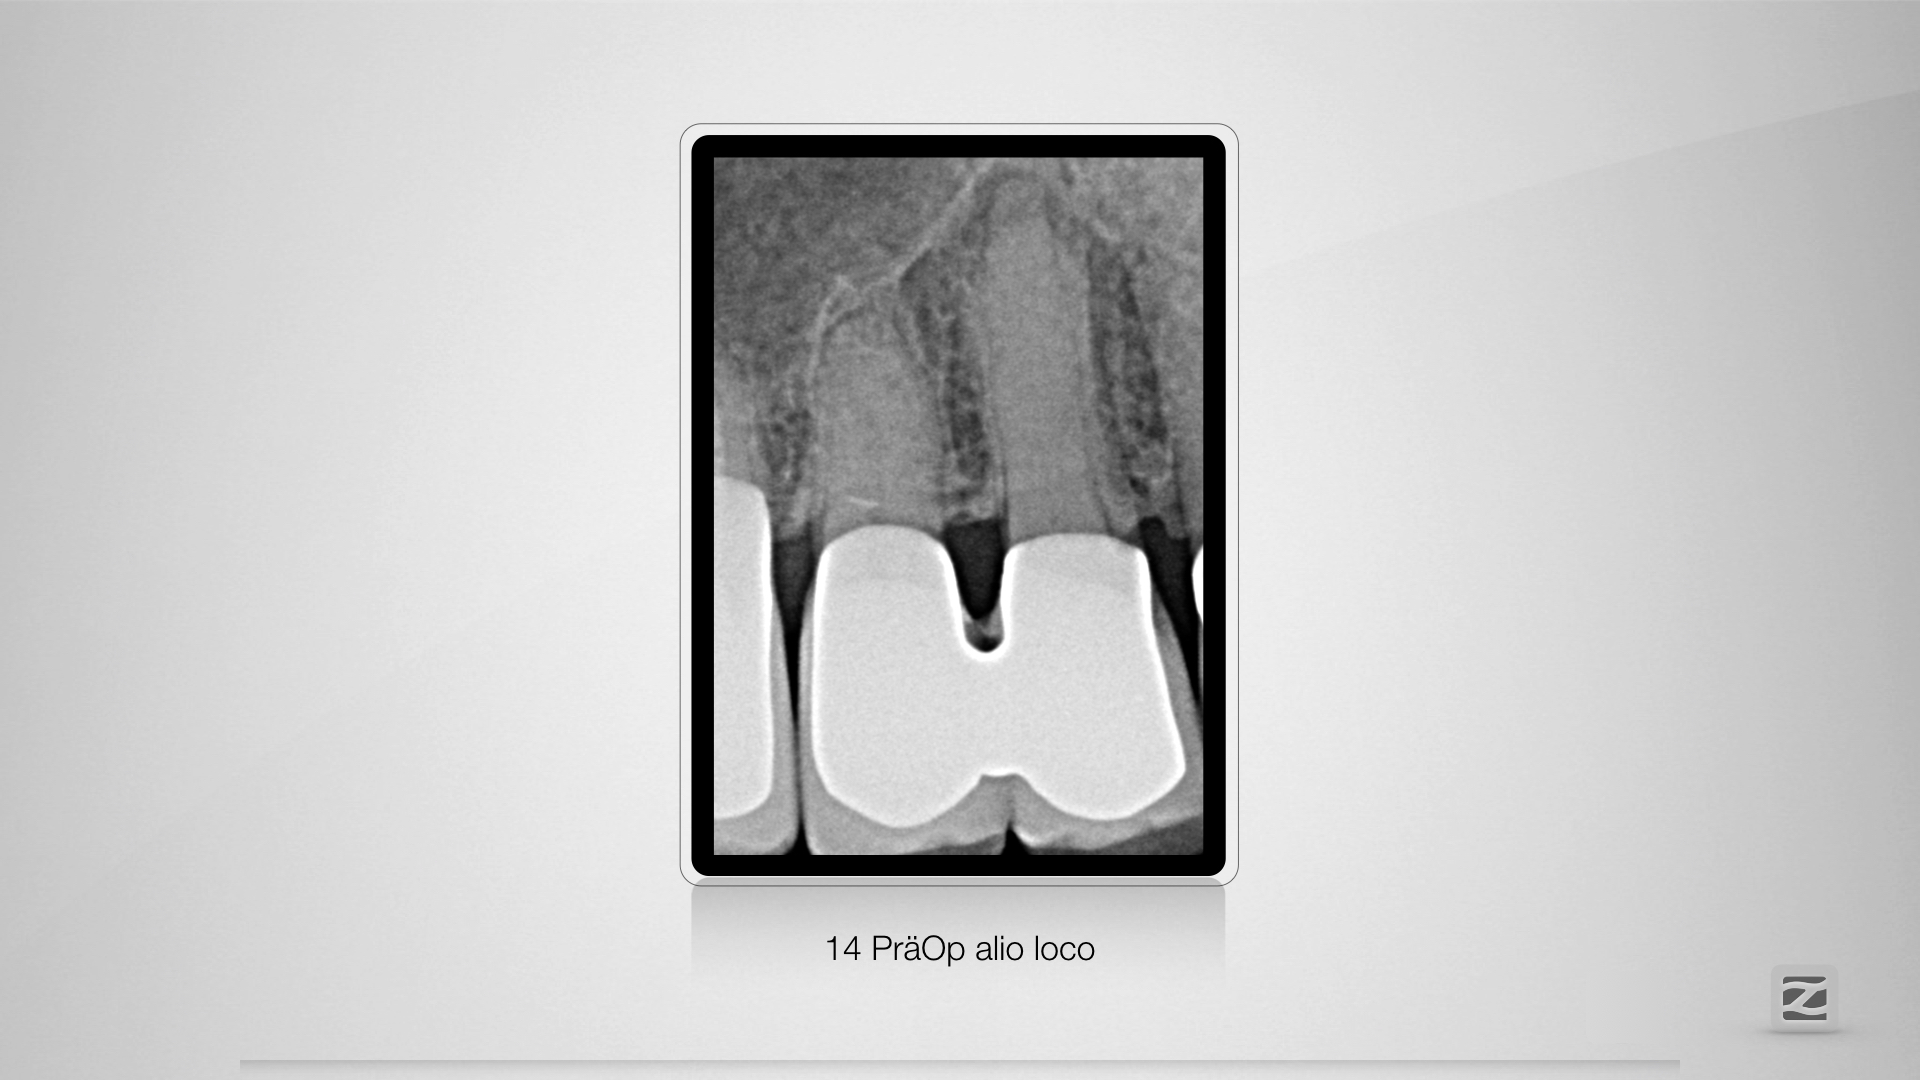

Dummheit gehört bestraft.